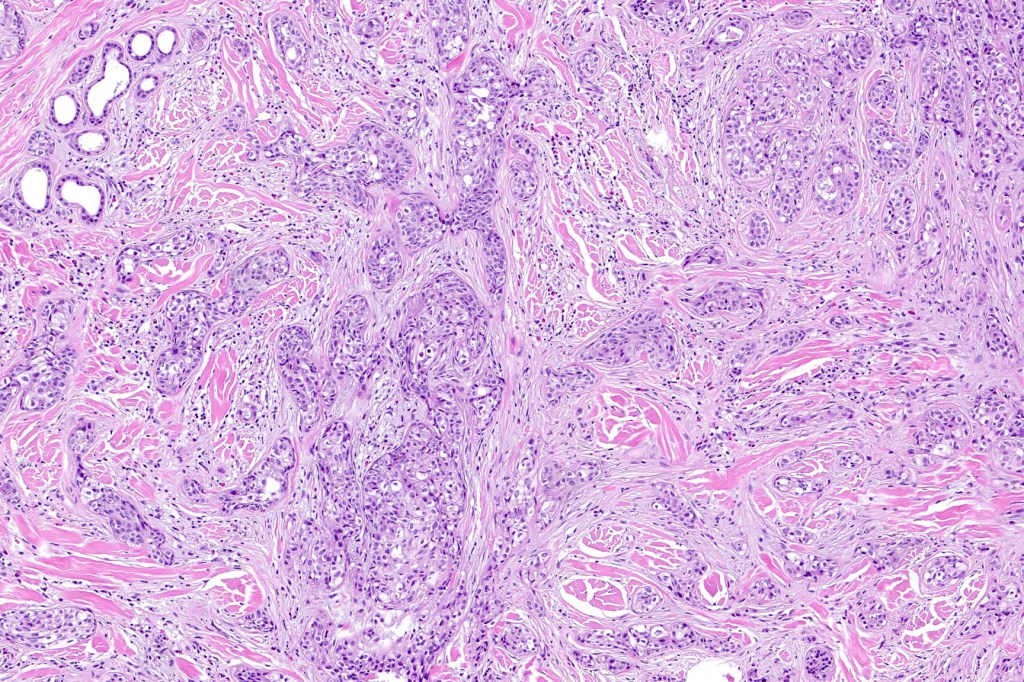

•Ulceration and solar elastosis are common

•Widely infiltrating biphasic tumor

•Superficial SCC

•Adenocarcinoma in deeper reaches

•Often extends to the subcutaneous fat

•Perineural infiltration is commonly seen